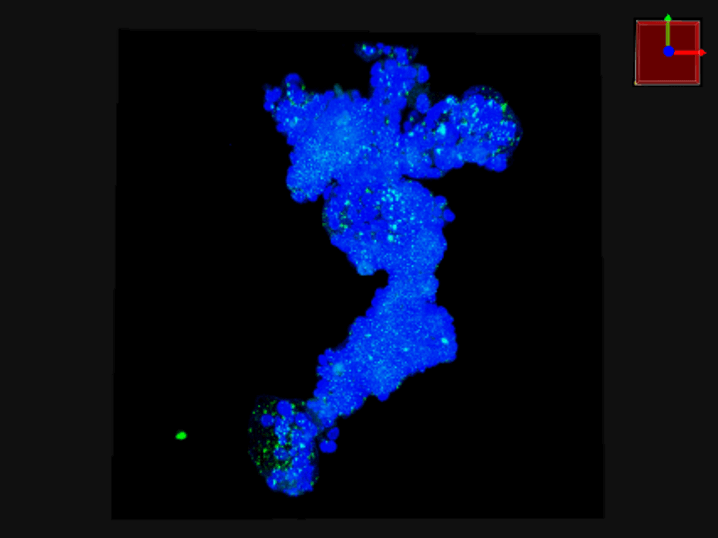

F-PDO®の3D解析

3D解析を用いた形態解析

青…DAPI(核を染色)

赤…actin(細胞骨格を染色)

緑…ZO-1(タイトジャンクションを染色)

3D解析を用いた形態的定量解析

- 青…DAPI(核を染色)

緑…Ki67(増殖細胞のマーカ) - 形態情報(細胞数、容積、Ki67陽性細胞数)を算出

- 細胞塊あたりの細胞数、細胞密度、増殖細胞の比率が算出することができる。

- F-PDO®の種類により、細胞塊の大きさ、細胞密度、増殖細胞の比率はさまざまである。